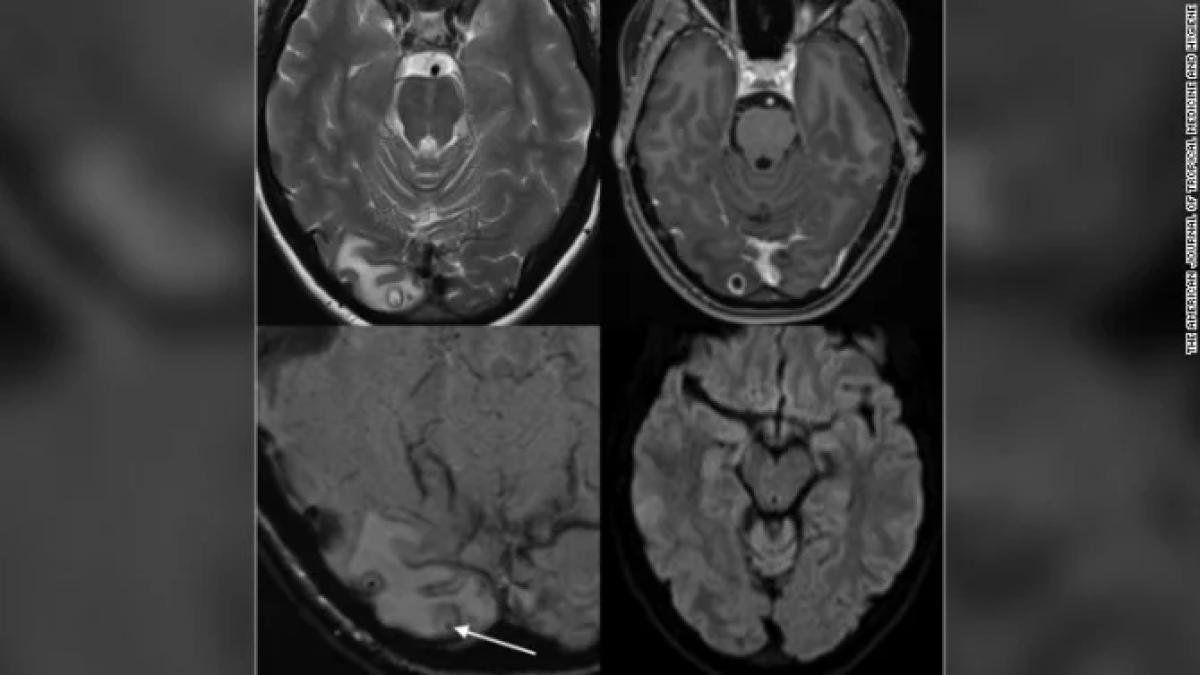

O echipă internațională de la Universitatea din Zurich a studiat informațiile genetice și scanările cerebrale ale mai mult de 25.000 de persoane pentru a înțelege modul în care caracteristicile genetice se corelează cu comportamentul de asumare a riscurilor, cum ar fi consumul de alcool, fumatul, condusul și promiscuitatea sexuală. Mărimea eșantionul le-a permis cercetătorilor să controleze mai multe variabile cum ar fi vârsta, sexul și alți factori pentru a dezvălui dacă există o legătură între funcția creierului, anatomie și comportamentul riscant.

Studiul, publicat în Nature Human Behavior, a confirmat că unele dintre zonele creierului se așteaptă să fie asociate cu un comportament riscant. Aceasta include hipotalamusul, unde sunt eliberați hormoni precum dopamina și cortexul prefrontal, care joacă un rol important în autocontrol și deliberarea cognitivă. Cea mai surprinzătoare descoperire a fost zona creierului numită cerebel, care nu este de obicei inclusă în studiile privind comportamentul de risc, deoarece este implicată în principal în funcția motorie fină. Studiul a constatat că cerebelul joacă de fapt un rol important în deciziile privind comportamentul de asumare a riscurilor.